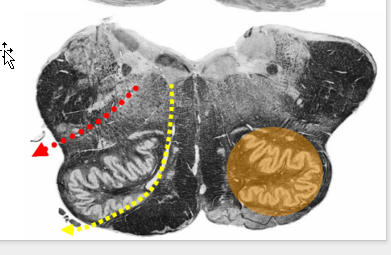

Describe the Rostral Medulla

@ level?

Appearance of?

What enlarges?

Structures and relationship to restiform body

between restiform body and Inferior olive.

Now Part of Restiform Body:

Reticular Formation Function

@ Level of CN IX & VIII

Appearance

dorsal and ventral cochlear nuclei (C.N. VIII)

Enlarges:

Restiform body

Reticular formation